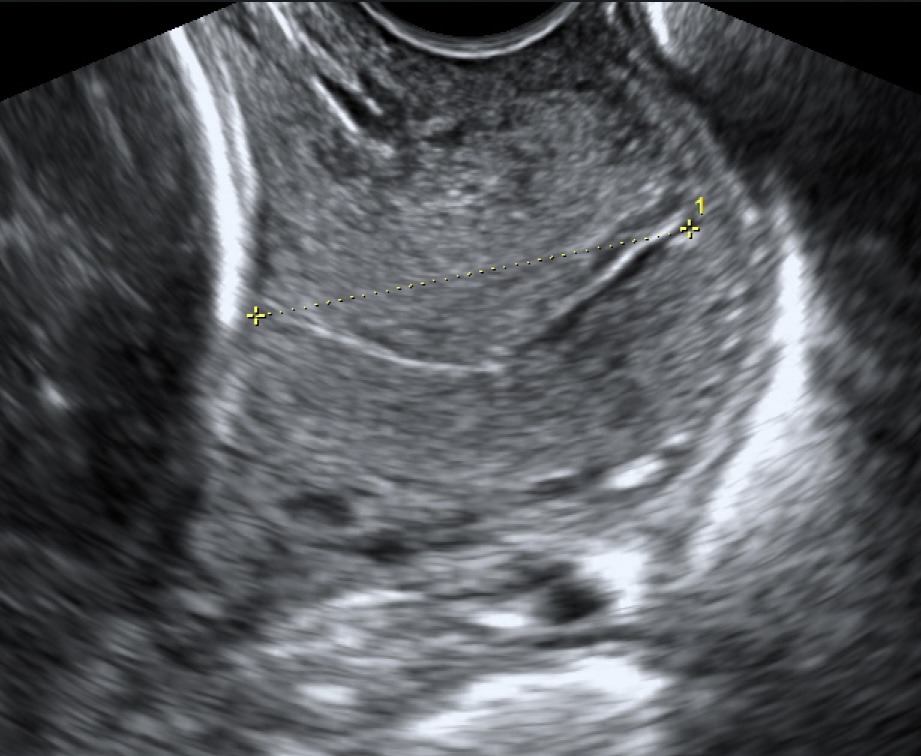

Cervicometría

Medición precisa de la longitud del cuello uterino mediante ecografía transvaginal, un estudio crucial para predecir y prevenir el riesgo de parto prematuro.